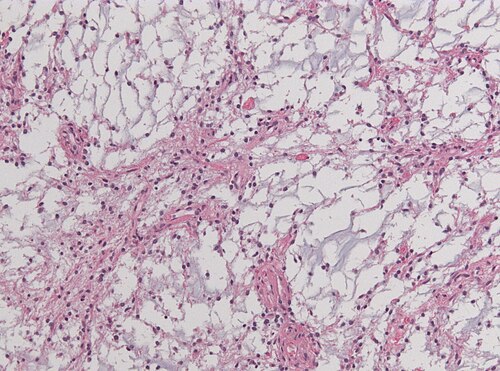

14 year old child with cognitive disturbances and hydrocephalus.

Left thalamus.

Intermediate magnification. H&E stain.

The elongated cell processes have a glial appearance

PILOMYXOID ASTROCYTOMA GRADE II WHO WITH KIAA1549(Exon15)-BRAF(Exon9) FUSION

Comment: Pilomyxoid astrocytomas are a variant of pilocytic astrocytoma and share the same genetic abberations such as KIAA1549-BRAF fusions as seen in the current case. They usually lack the typical compact areas with rosenthal fibers seen in pilocytic astrocytomas. The tumors have been designated as WHO grade II tumours in the 2007 WHO classification, because of their tendency to recur more often.[1] A hypothalamic/chiasmatic location itself is a adverse prognostic factor.[2]